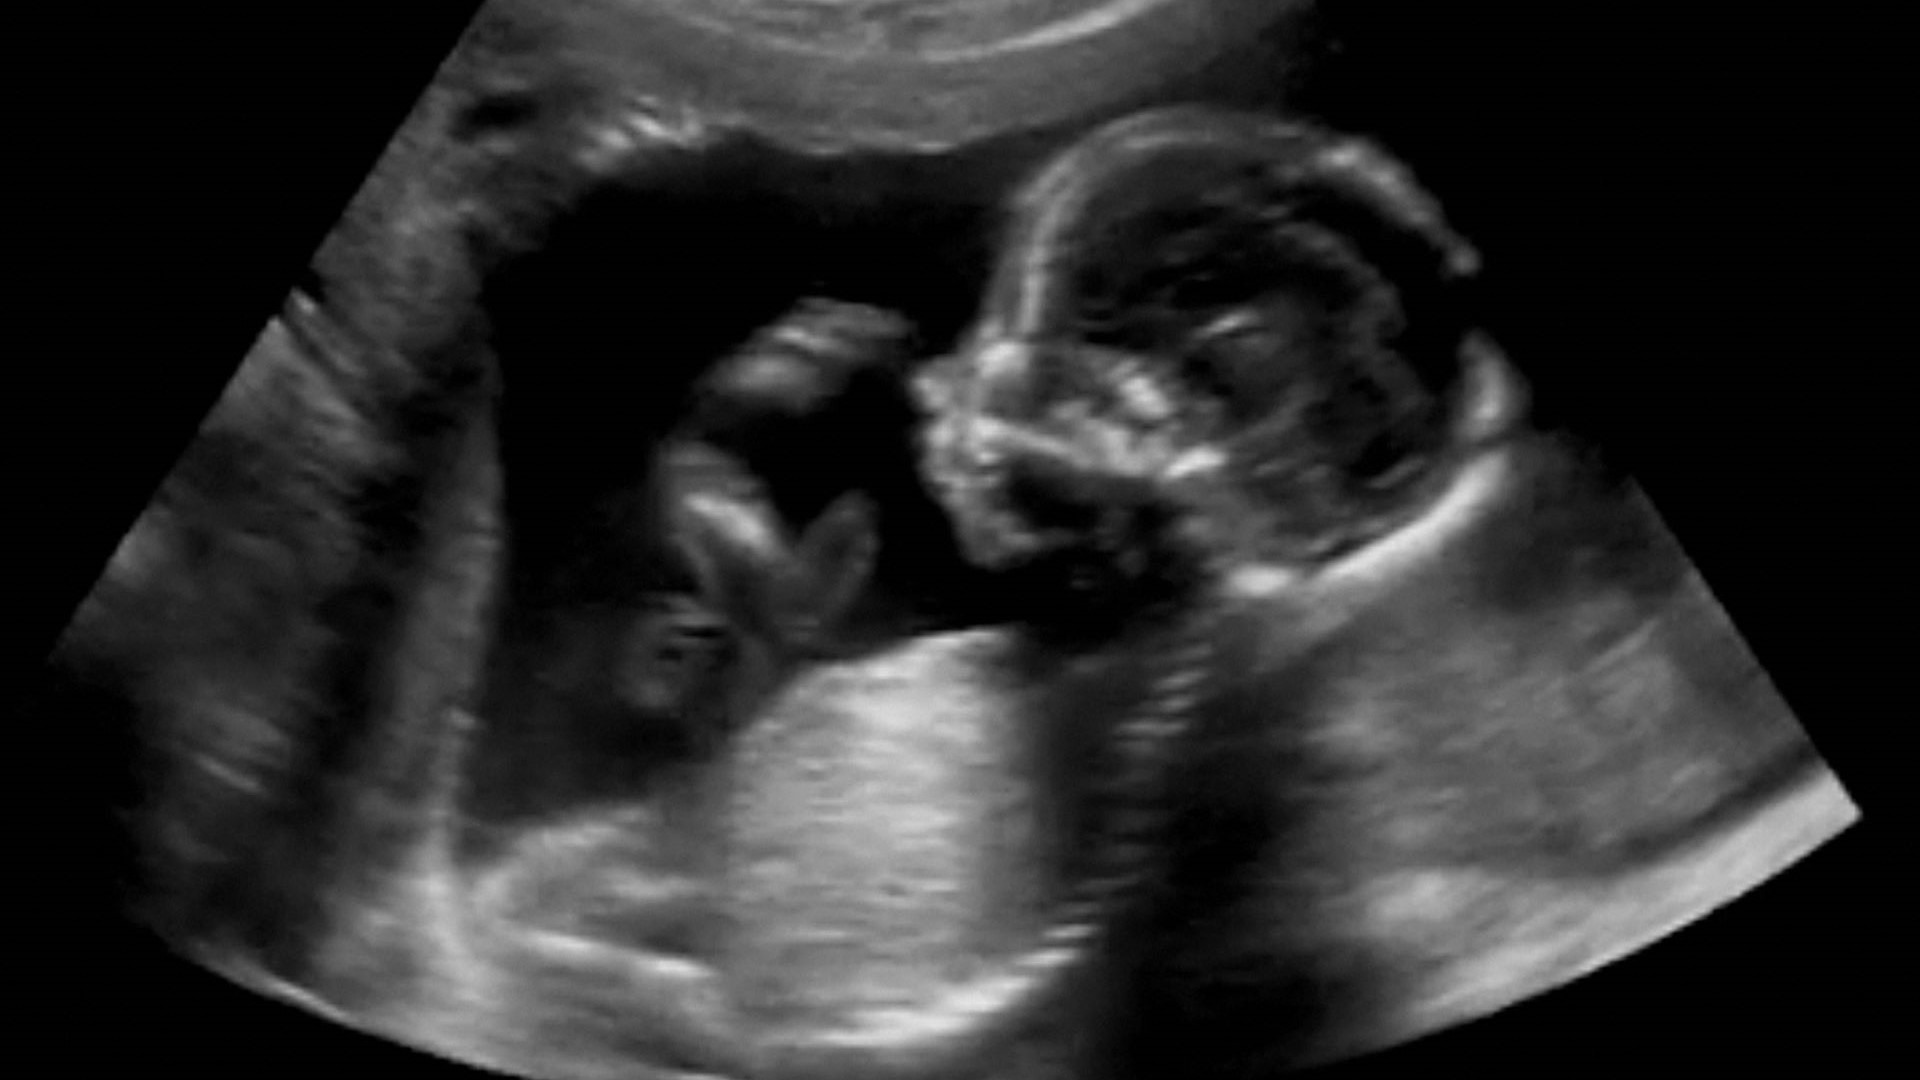

De post-bacheloropleiding voor structureel echoscopisch onderzoek biedt een diepgaande training voor het uitvoeren van gedetailleerde tweede trimester screenings. Deze opleiding omvat zowel theorie als praktijk en stelt professionals in staat om zelfstandig echoscopische onderzoeken uit te voeren bij zwangerschappen tussen de 18 en 21 weken. Deelnemers krijgen de kans om hun vaardigheden te ontwikkelen door te oefenen met echte modellen, wat essentieel is voor het nauwkeurig beoordelen van de ontwikkeling van het ongeboren kind.

De post-bacheloropleiding 'Structureel Echoscopisch Onderzoek tweede trimester' biedt diepgaande kennis en praktische vaardigheden voor het uitvoeren van een tweede trimester screening. Deze screening is cruciaal voor het beoordelen van de groei en ontwikkeling van het kind, evenals het identificeren van mogelijke lichamelijke afwijkingen.

De opleiding combineert theorie met hands-on praktijklessen in kleine groepen, waarbij echte zwangere vrouwen als modellen dienen om de vaardigheden te verfijnen. Na afronding van deze opleiding ben je in staat om zelfstandig een volledige screening uit te voeren.

Je leert kijken naar:

- de groei van het kind

- de ontwikkeling van de organen en

- of het kind lichamelijke afwijkingen heeft zoals een open rug, open schedel, waterhoofd, hartafwijkingen, gat in het middenrif, gat in de buikwand, afwijking van de nieren of afwijking van de botten.